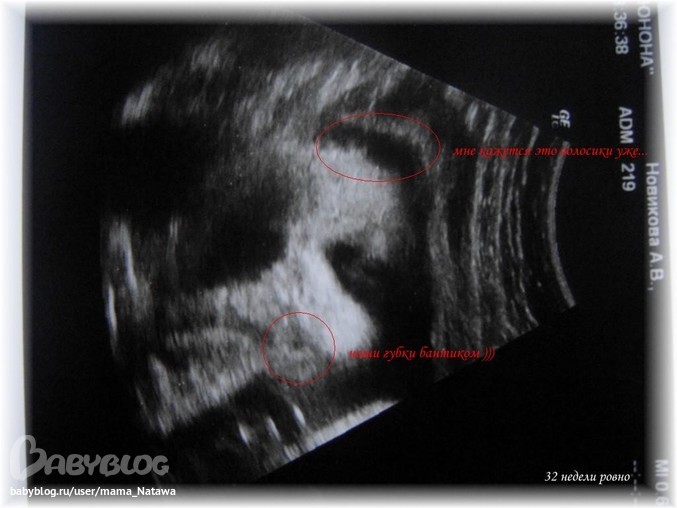

Самое интересное в том, что нам удалось рассмотреть личико - на сколько это возможно

Губки у нашего малыша как у папы в детстве!!! БАНТИКОМ!!! Прям бантик и посередине дырочка

У мужа на детских фотках тоже самое ))) как куклёныш!!! Глазки вроде большие ))))))))) дай Бог, чтобы моиииииииии

А вот и наше сокровище

Это фотка личика ))) есть ещё туловища - но там ничего непонятно... а тут прям видно всё!!! Носик, губки, глазки )))